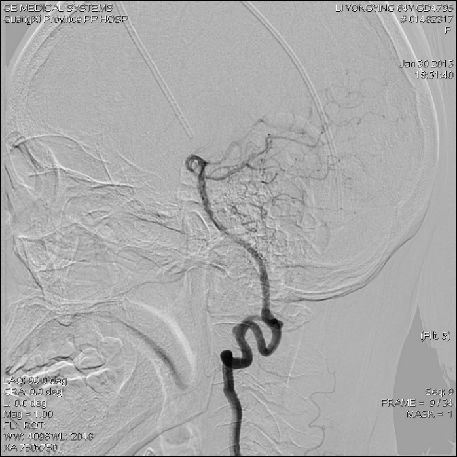

2015-1-30 DSA

在局麻下行腰椎穿刺术+ 测脑压术,患者取左侧卧位,测量脑脊液压力为60mm水柱。